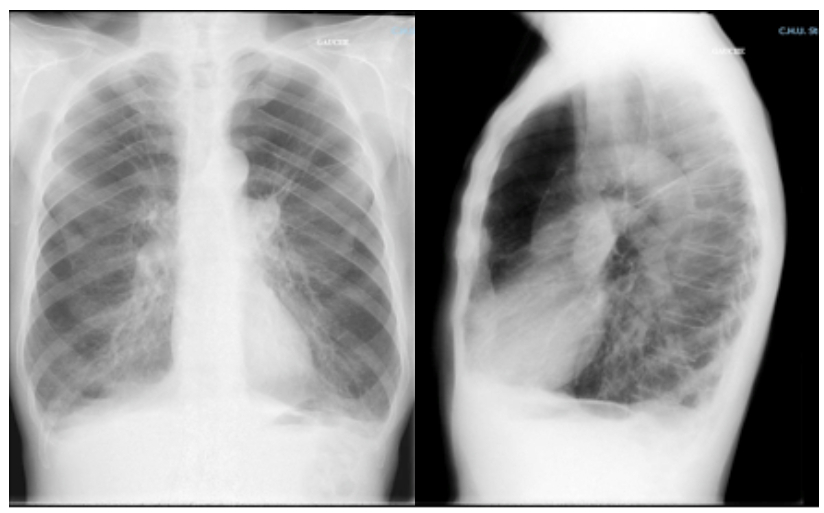

Le patient retourne à domicile. Il est suivi par un pneumologue qui le revoit à 6 mois de son hospitalisation. Il reste très symptomatique malgré le traitement de fond par bronchodilatateur de longue durée d’action seul bien conduit et la réhabilitation respiratoire. Il se plaint beaucoup d’un encombrement bronchique avec bronchorrhée. Il n’a pas refait d’exacerbation ces 6 derniers mois. Entre-temps il a vu un cardiologue qui lui a prescrit un bêtabloquant cardio-sélectif. Le pneumologue lui prescrit un scanner qui est le suivant.

Figure 5.

Il s’agit ici d’un emphysème bulleux typique : zones d’hypodensité traduisant une raréfaction du parenchyme pulmonaire. On parle de bulle quand les zones d’hypodensité sont cerclées par une paroi fine et ont un diamètre de plus de 1 cm.